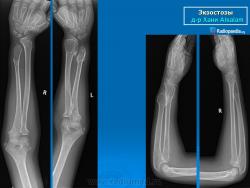

Локализация остеохондромы: частота поражения отдельных костей различна; нижний коней бедренной кости, верхние отделы плечевой и большеберцовой костей поражаются более чем у половины больных. На всем протяжении остеохондрома покрыта надкостницей. Она может быть обнаружена и в других костях, за исключением костей лицевого черепа. Все же поражение костей позвоночника, кистей рук и стоп встречается редко. При рентгенологическом исследовании видна типичная картина узкого или широкого выроста вблизи эпифизарной части пораженной кости. Обычно плотность узла неоднородная, имеются многочисленные плотные участки, соответствующие обызвествленным хрящевым долькам. Хрящевая «шапочка» большей частью не определяется, поскольку хрящ остается необызвествленным. Она может быть выявлена только при магнитно-резонансной томографии.